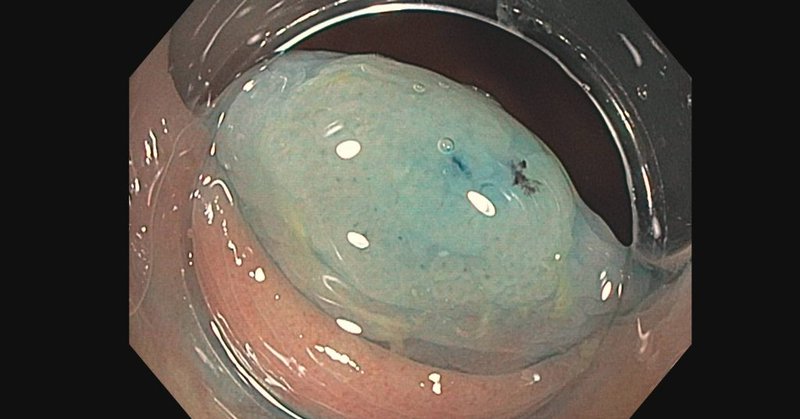

Thrilled to receive the ASGE outstanding manuscript award for our VGIE paper demonstrating a novel approach to treating buried bumper syndrome! Beyond thankful to my co-authors and mentors Dr. Storm and Dr. Buttar.🙏 Can’t wait to celebrate at #DDW2025! @ASGEendoscopy 🎉